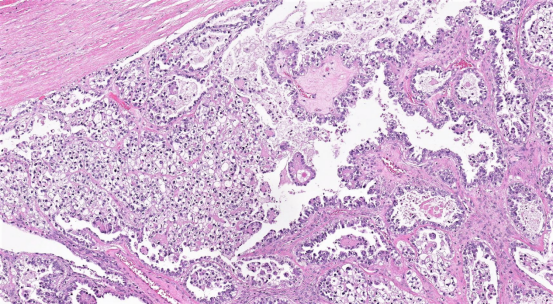

导读:卵巢透明细胞癌(OCCC)是一种相对罕见的上皮性卵巢恶性肿瘤,具有独特的临床、组织病理学和遗传学特征。晚期OCCC患者预后较差,且对标准化疗耐药。那卵巢透明细胞癌国外能治好吗?卵巢透明细胞癌在美国能治好么?美联医邦作为拥有8年海外就医服经验的美国本土出国看病服务机构,本篇为大家总结了2023-2024年度卵巢透明细胞癌的国际新疗法。同时分享了一例国内罕见肿瘤卵黄囊癌患者与安德森癌症中心专家视